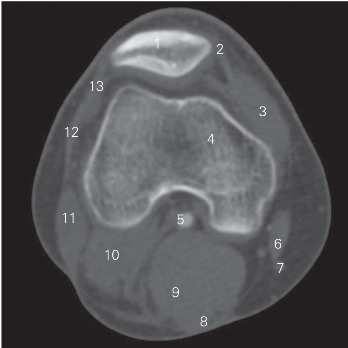

图5-19 经髌骨的横断层CT图像(骨窗)

1 髌骨 patella 2 内侧支持带 medial retinaculum

3 股内侧肌 vastus medialis 4 股骨 femur

5 腘动、静脉 popliteal artery and vein

6 缝匠肌 sartorius 7 股薄肌腱 gracilis tendon

8 半腱肌 semitendinosus 9 半膜肌 semimembranosus

10 腓肠肌外侧头 lateral head of gastrocnemius

11 股二头肌 biceps femoris 12 髂胫束 iliotibial tract

13 外侧支持带 lateral retinaculum